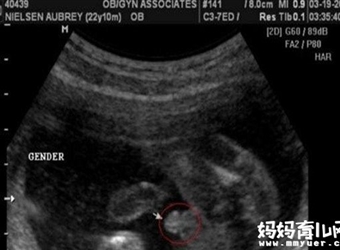

要知道,在做B超时医生当然不会告诉你腹中胎儿的性别,(这也是国家明文规定的)那要怎么才能知道谜底呢?四维数据怎么看男女的方法,想知道答案的朋友们,一…

宝宝的性别早在受精卵结合的那一刻就决定了,只是在后来的发育中生殖器才逐渐形成,怀孕5个月的时候,胎宝宝的生殖器已经形成,可以通过B超看胎儿性别。5个月B…

做完四维彩超后,医生会当场给你一张彩超单,上面有胎儿发育的数据,还有网上疯传的男孩女孩的标志。这让准妈们迫不及待地拿出自己的彩超单一看究竟,女孩的标…